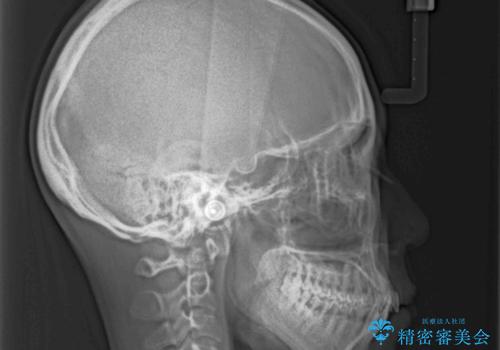

通常であれば、上下顎左右小臼歯各1歯の合計4本を抜歯しますが、歯肉退縮の著しい下顎前歯を抜歯して欲しいという患者様の強い希望により、上顎のみ左右小臼歯2歯を、下顎は前歯を1歯を抜歯することとしました。

抜歯する歯を変更したため奥歯の咬合はアンバランスとなりましたが、前歯は綺麗に整い、歯肉退縮も回避できました。